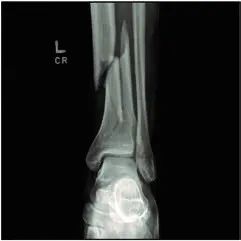

1.切口负压治疗与标准伤口敷料对严重创伤合并下肢骨折术后深部手术部位感染的影响: WHIST随机临床试验(JAMA 2020; 323:519–26)

85%的严重创伤患者存在严重的肢体损伤,其中骨折最常见。严重创伤引起的全身性炎症反应合并骨折临近部位的软组织损伤,可导致伤口深部感染。

本研究比较了伤口负压治疗与标准敷料覆盖在降低严重创伤性下肢骨折手术相关的伤口深部感染率方面的效果。

随机选取1548名患者(平均年龄50岁),其中有1519名(98%)患者的主要结果数据可纳入研究。

术后30天深部手术部位感染率无明显差异。在伤口负压治疗组中30天深部伤口感染率为5.84%(770例中有45例),而在标准敷料组中感染率为6.68%(749例中有50例)(OR 0.87 [95% CI,0.57-1.33];绝对风险差异ARD -0.77% [95% CI,–3.19-1.66%];P = 0.52)。

对实际应用的敷料类型的方案数据分析得出了类似结果:伤口负压治疗组的感染率为6.14%,而标准敷料组的感染率为6.57%(OR 0.93 [95% CI,0.6 -1.44];ARD 0.33% [95% CI,–2.93-2.15%];P = 0.76)。术后90天感染率两组间也无差异。

(文章选择:Martin J. London;图片:J. P. Rathmell)

关键信息:该研究提示,对于因严重创伤导致的下肢骨折而接受手术的患者,伤口负压治疗与标准敷料覆盖对于深部手术部位感染方面并无显著差异。